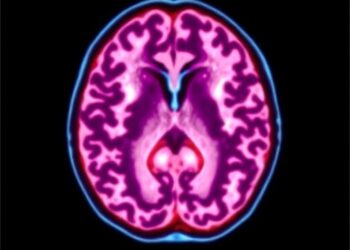

Albumin Plus Endovascular Therapy Boosts Stroke Outcomes

In a groundbreaking advancement for stroke therapy, a recent randomized clinical trial published in Nature Communications brings to light the ...